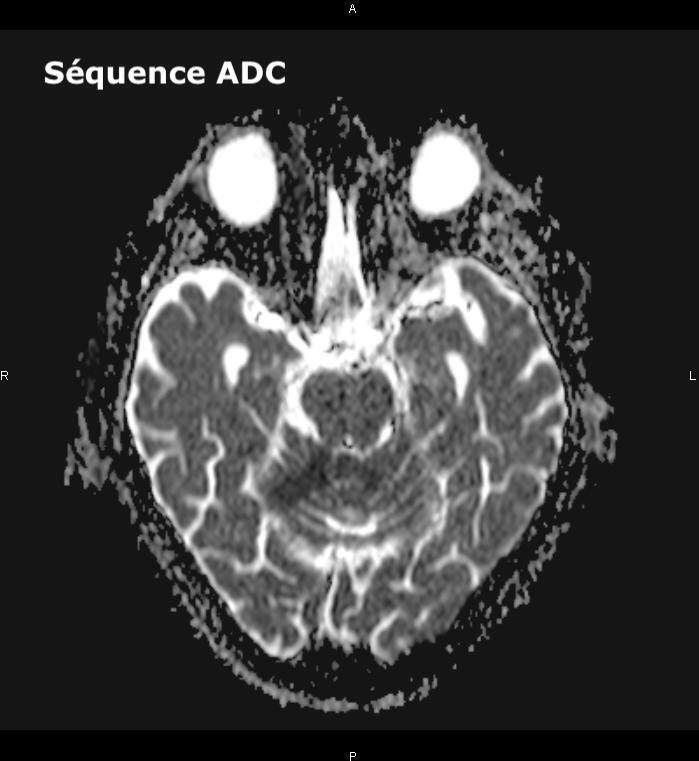

Un ou plusieurs déficits neurologiques (ataxie cérébelleuse, paralysie faciale) d’apparition soudaine (et le plus souvent d’emblée maximale), focale (tous les signes peuvent ici être expliqués par l’atteinte d’un seul territoire artériel) doivent faire évoquer le diagnostic d’AVC, et doivent conduire à une imagerie cérébrale rapidement.